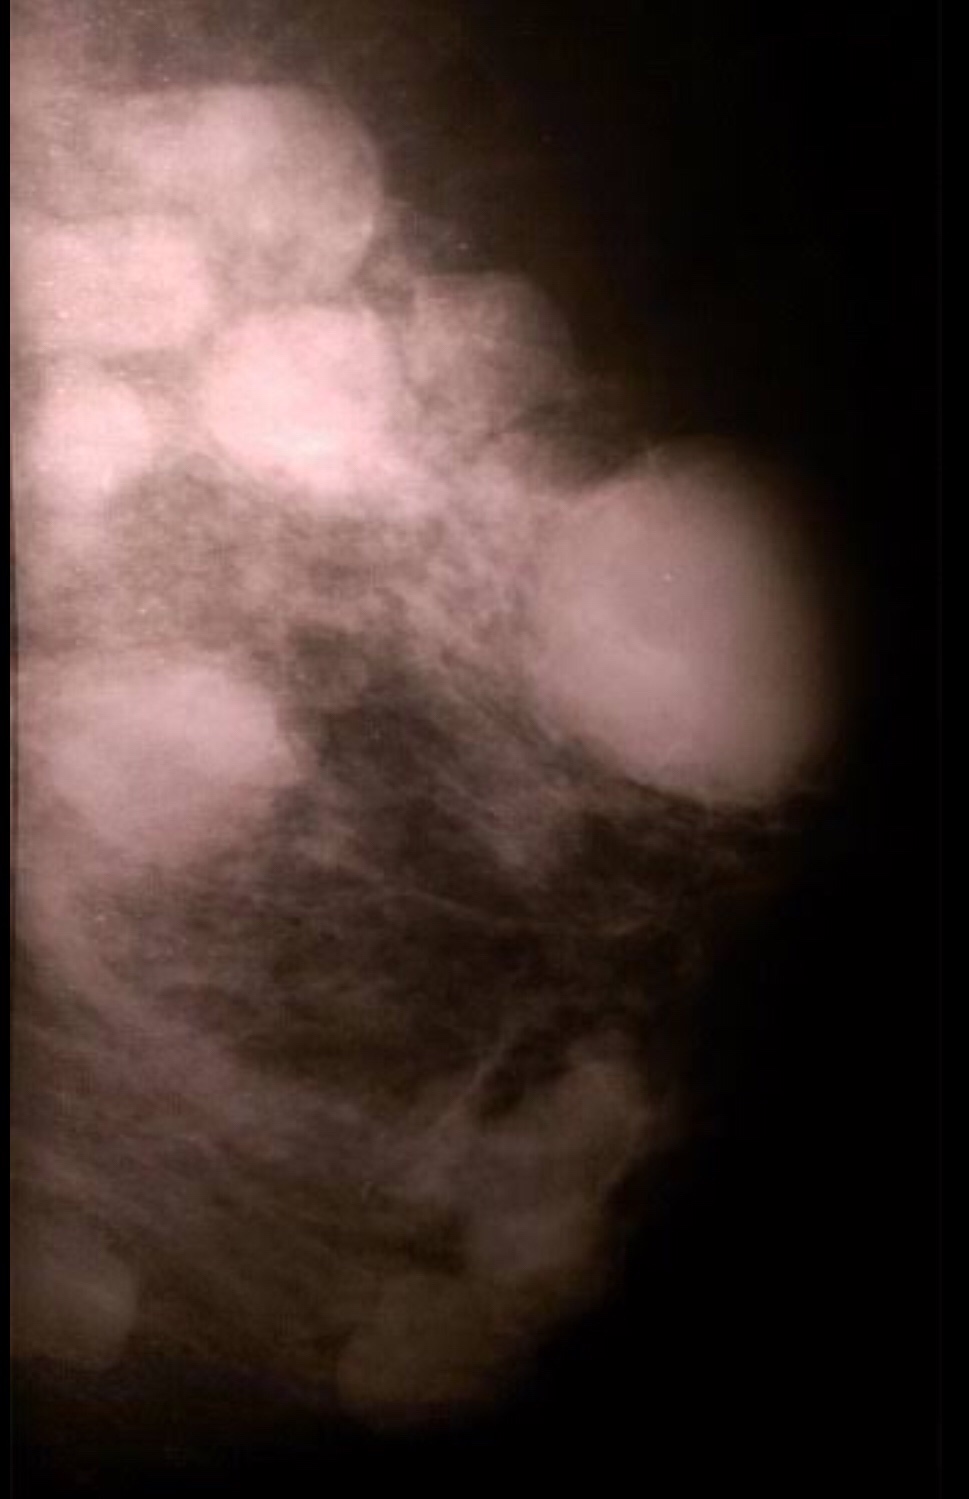

Fibroadenoma- is referred to as the Breast mouse- most often is detected as a small lump that moves inside the breast. They may be single or multiple as on the picture on the right below! The lumps are smooth walled and well defined.

Breast Implants: Breast augmentation is one of the most common and popular cosmetic surgeries that women undergo. This is how they would appear on the mammogram.

Breast implants make mammography more difficult and can obscure small lesions. Mammography can also help detect implant related problems such as rupture, capsular contraction etc.